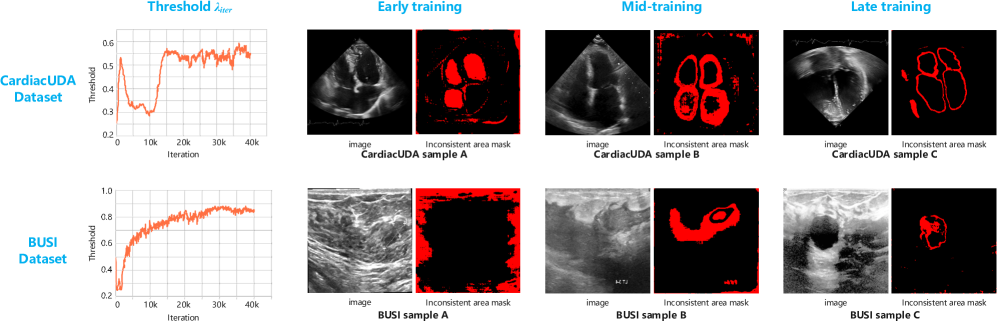

Firstly, we need to decouple the inconsistent parts predicted by the two network branches. Given that the prediction confidence and the quality of pseudo-labels are continually evolving during training, a dynamic threshold [47] is required to determine the regions of inconsistency. In the initial training phase, the threshold should remain as low as possible to retain more uncertain regions, promoting pseudo-label diversity and preventing the model from converging to local optima by prematurely relying on a limited set of high-confidence samples. The threshold is expressed as follows:

λiter=η1Bb=1B(1𝐔)+(1η)λiter1,\lambda_{iter}=\eta\frac{1}{B}\sum_{b=1}^{B}{(1-\mathbf{U})}+(1-\eta)\lambda_{iter-1}\text{,} (12)

η=iteritermax,\eta=\frac{iter}{iter_{max}}\text{,} (13)

where iteriter represents the current iteration index, η\eta is a weight that increases with the iteration of training, BB denotes the batch size, and 𝐔W×H\mathbf{U}\in{\mathbb{R}^{W\times{H}}} is the normalized uncertainty map. The thresholds for 𝐔cnn\mathbf{U}_{cnn} and 𝐔mamba\mathbf{U}_{mamba} are defined as λitercnn\lambda_{iter}^{cnn} and λitermamba\lambda_{iter}^{mamba} respectively. To promote diversity in pseudo-labels, we select the smaller one among them as the final threshold. Furthermore, The threshold is initialized to 1C\frac{1}{C} (i.e., λ0=1C\lambda_{0}=\frac{1}{C}), where CC is the number of classes. Thereby, the threshold is finally adjusted as:

λiter={1Citer=0,fmin(λitercnn,λitermamba)otherwise,\lambda_{iter}=\left\{\begin{matrix}\frac{1}{C}&iter=0\text{,}\\ f_{min}\left(\lambda_{iter}^{cnn},\lambda_{iter}^{mamba}\right)&\text{otherwise}\text{,}\end{matrix}\right. (14)

where fmin()f_{min}(\cdot) denotes the acquisition of the minimum value.